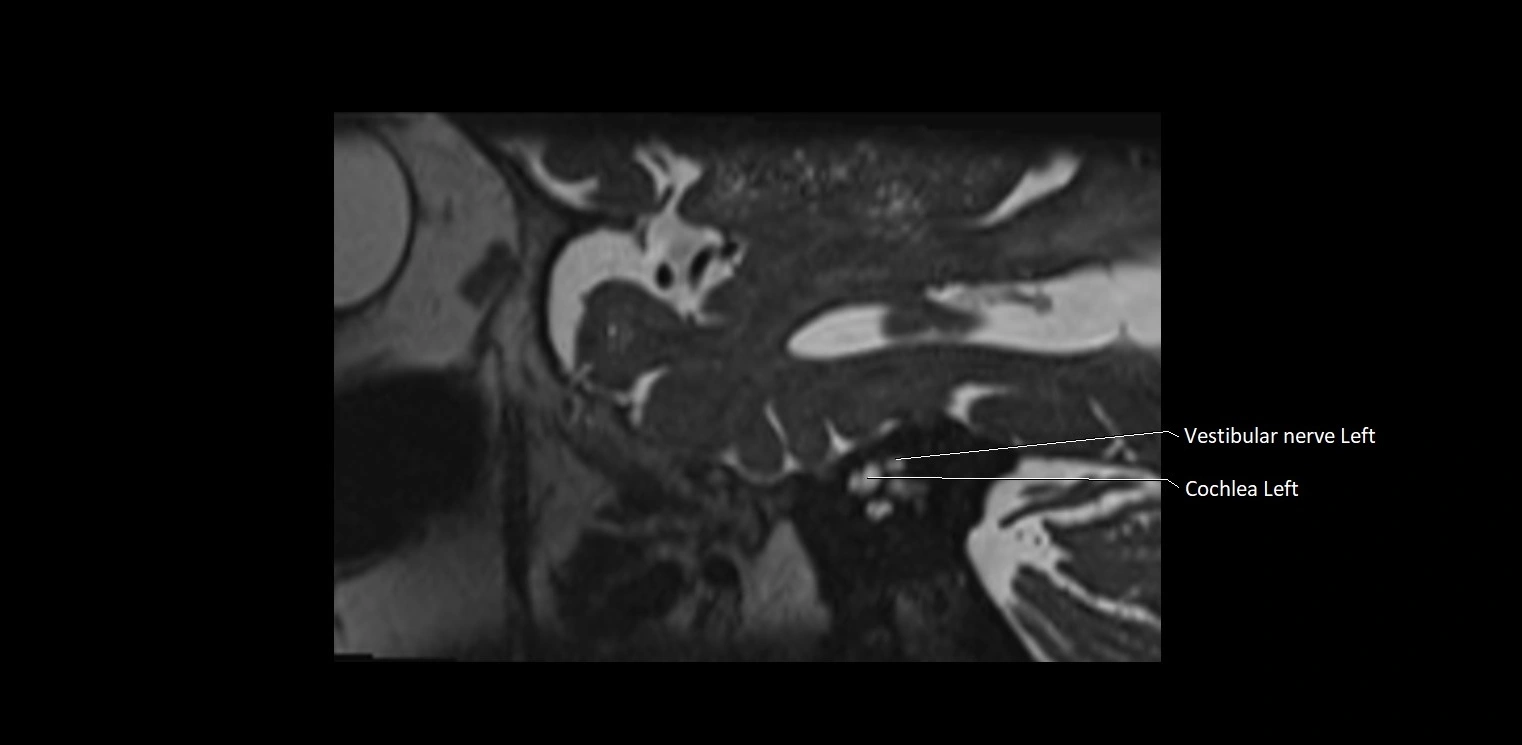

MRI Appearance

• The abducens nerve is a small, thin, linear structure

• Best visualized on high-resolution T2-weighted 3D MRI sequences (e.g., FIESTA or CISS)

• Seen as a hypointense (dark) line running from the brainstem at the pontomedullary junction, traversing the prepontine cistern, and entering Dorello’s canal under the petrosphenoidal ligament, then into the cavernous sinus, and finally the orbit

• May be challenging to visualize in standard MRI due to its small size

• Pathology may be inferred by absence, displacement, or enhancement of the nerve

MRI images

image